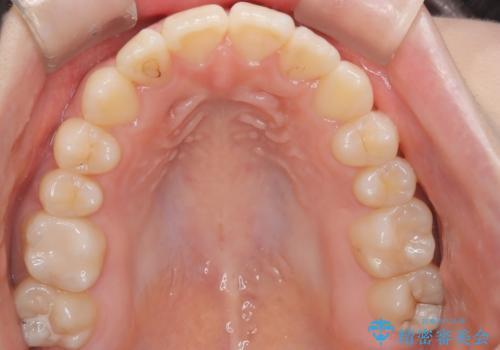

マウスピース矯正で前歯のガタツキを改善! 短期間で治療完了

- 前歯のガタツキが気になるとのことで来院されました。

前歯のガタツキに加え、奥歯の噛み合わせにも問題があったため、マウスピース矯正で治療し改善しました。